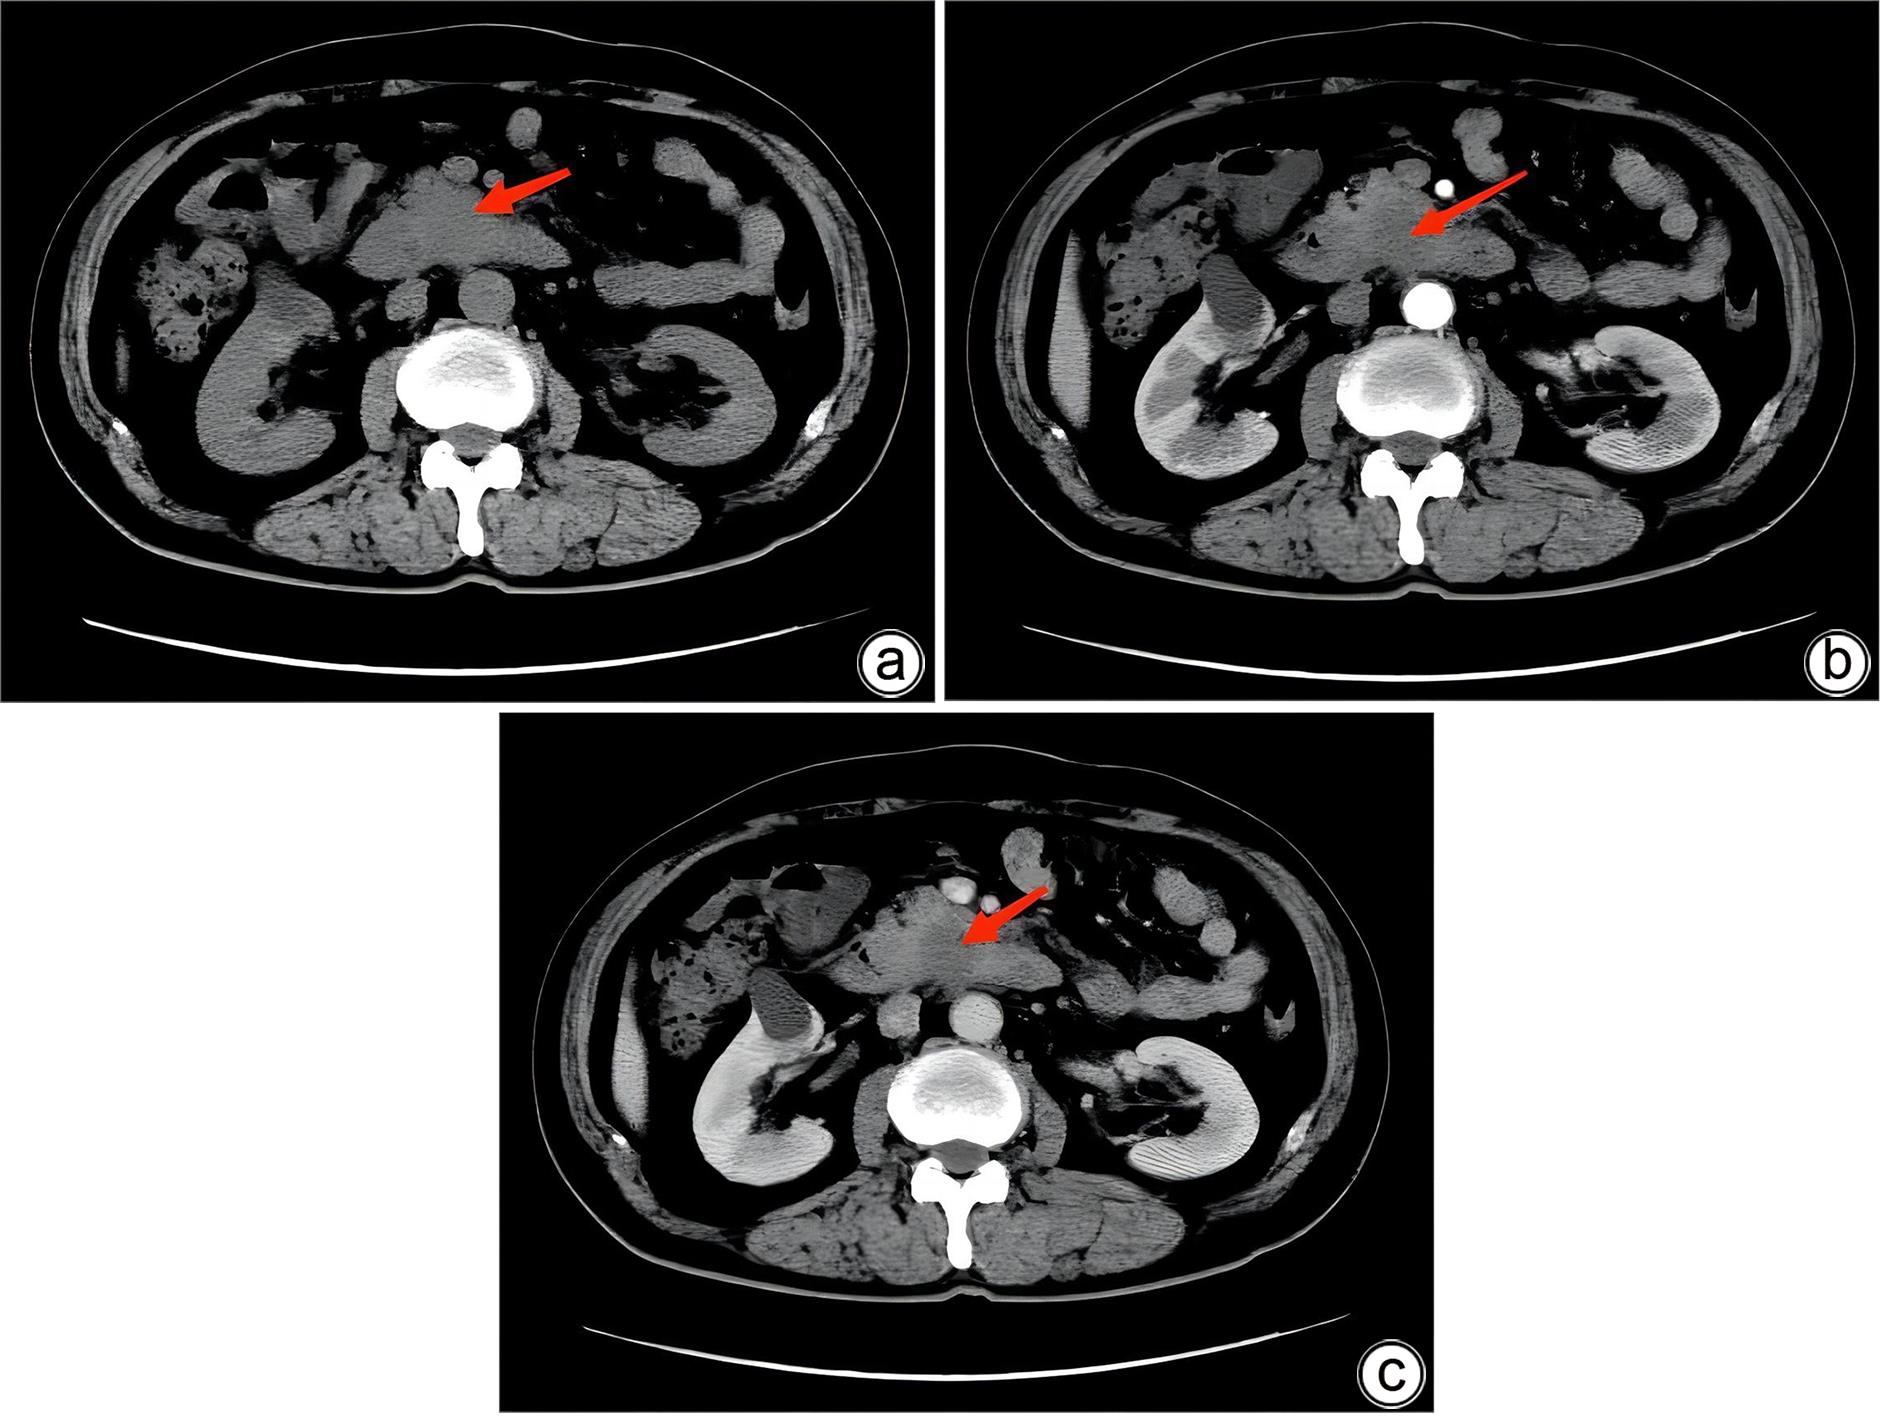

Misdiagnosis of intrapancreatic accessory spleen: A report of two cases

Mengzhe ZHANG, Jie RAO, Zhengle ZHANG

2024, 40(2): 365-368. DOI: 10.12449/JCH240223

Abstract(1384) HTML (333) PDF (1188KB)(176)

Abstract:

Accessory spleen refers to the spleen tissue that exists outside of the normal spleen, with a similar structure to the main spleen and certain functions. Intrapancreatic accessory spleen (IPAS) completely enveloped by the pancreas has an incidence rate of only 2%, and it is easily misdiagnosed in clinical practice due to its atypical clinical symptoms and similar radiological features to pancreatic neuroendocrine tumor, pancreatic solid pseudopapillary tumor, and other pancreatic space-occupying lesions. This article reports the clinical data of two patients with IPAS who were misdiagnosed as pancreatic neuroendocrine tumor and pancreatic solid pseudopapillary tumor, respectively, analyzes the reasons for misdiagnosis, and summarizes the experience in diagnosis and treatment, in order to improve the ability for the differential diagnosis of IPAS in clinical practice.